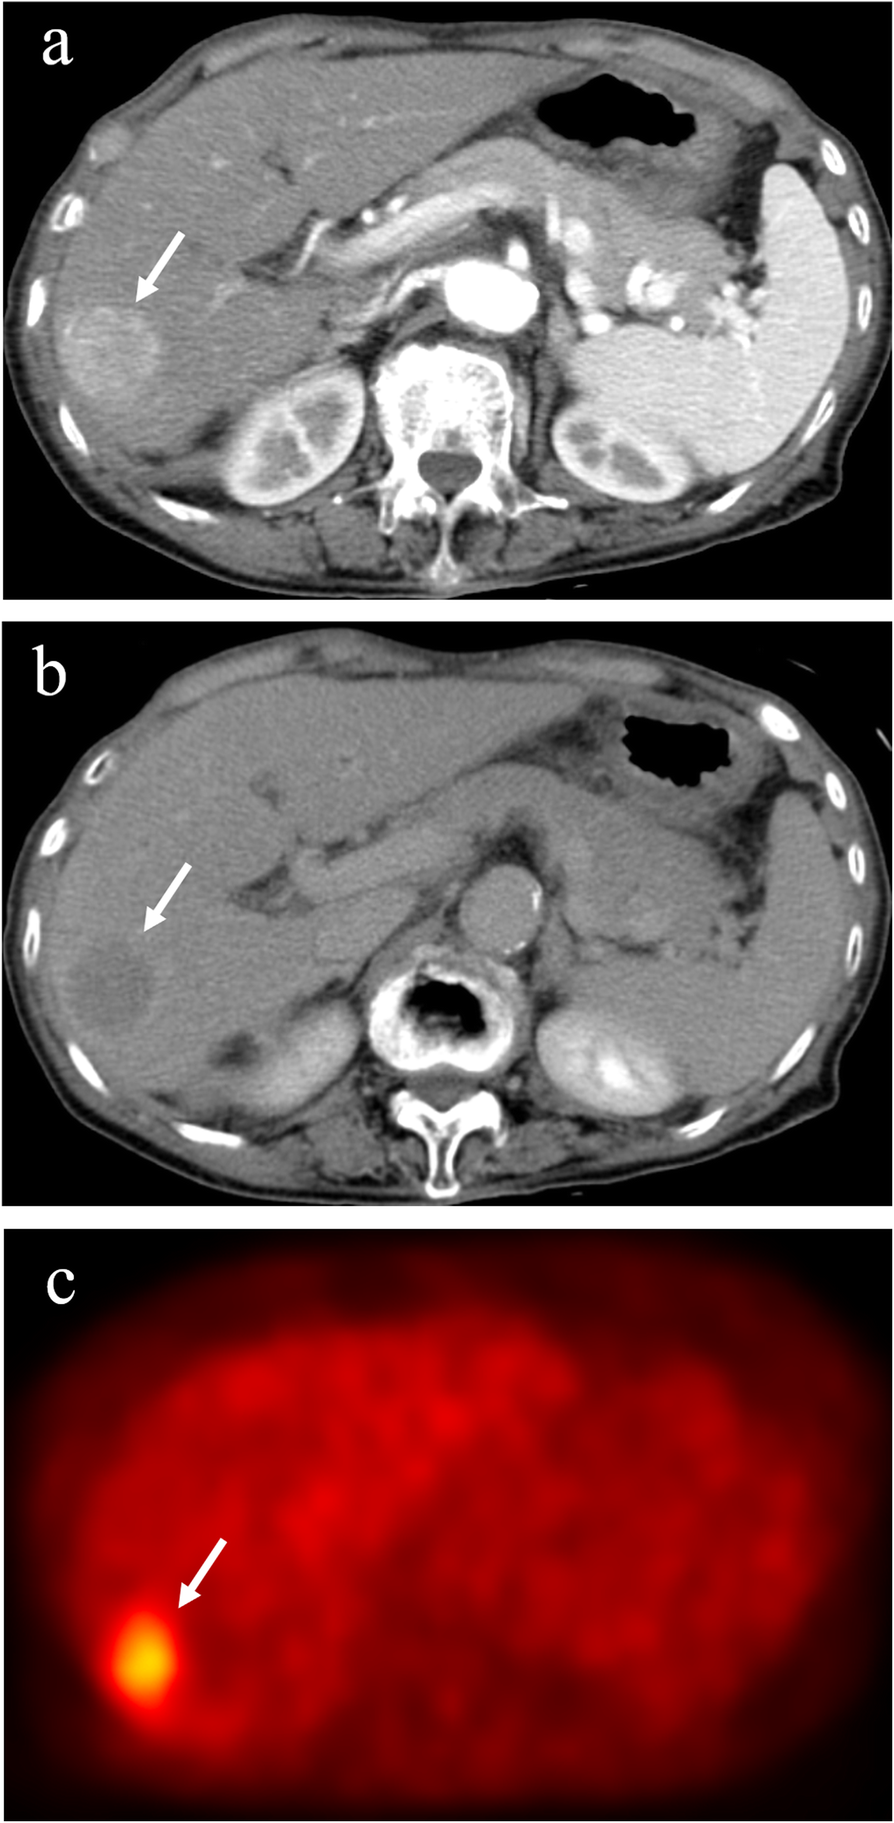

Hepatocellular carcinoma with positive 18F-fluorodeoxyglucose uptake on positron emission tomography. The hepatocellular carcinoma (diameter, 3.0 cm) in segment 5 exhibits staining during the arterial phase of contrast computed tomography (a) and washout during the equilibrium phase (b). The tumor has higher 18F-fluorodeoxyglucose uptake than that of surrounding liver on positron emission tomography (c). Arrows indicate the tumor. 18F-FDG, 18F-fluorodeoxyglucose; PET, positron emission tomography